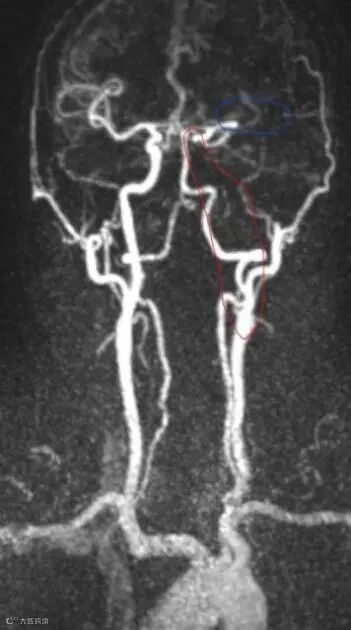

南京市第一医院是国家卫生健康委首批高级卒中中心,设有独立的神经内科急诊及脑血管病绿色诊疗通道。接诊的侯建康主治医师第一时间启动绿通,完善了头部磁共振及血管成像检查,明确了王先生急性缺血性脑梗死的诊断,而梗死原因是王先生脑内两根非常重要的血管(左侧颈动脉和左侧大脑中动脉)发生了堵塞。

手术过程中,侯建康主治医师发现了王先生血管堵塞的前因后果:左侧颈动脉形成了动脉夹层,夹层进一步诱发血栓形成;而形成的血栓被血流冲刷脱落,进一步堵塞了远端的大脑中动脉。在施洪超主任医师指导下,侯建康主治医师使用抽吸导管将脱落到大脑中动脉的血栓抽吸了出来,随后在动脉夹层的部位植入了一枚支架以重建管腔。

两根堵塞的血管均被重新开通,脑组织迅速得到了血液供应,王先生得救了!